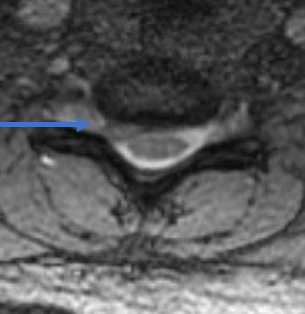

32 year old female comes with right arm pain that radiates all the way down to her fingers. We tried therapy, injections, oral pain medicine, and time. Because of the pain, a MRI showed a herniated disc in her neck on the right side (arrow). The left image is a side view and the right images is a cross section view.

She underwent a minimally invasive anterior cervical discectomy and fusion after removing the herniated disc. A MRI shows resolution of the herniated disc.